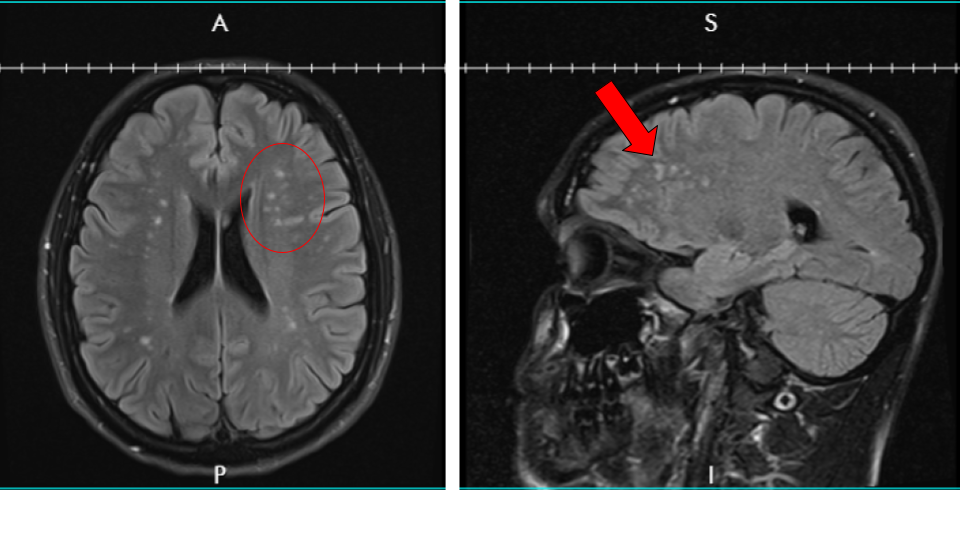

After weeks of trying to get an appointment, I finally saw the doctor and he ordered a bunch of tests including an EEG and an MRI. The EEG was normal. The MRI was not. The MRI revealed that I had lesions on my brain. A lot of them. I had more tests after that including a spinal tap to check for MS but nothing that revealed anything specific. The neuro gave up and said he couldn’t help me so I found a couple more, which took months to schedule.

Finally, in October, it looks like we may have finally found the answer to my symptoms. A genetic test revealed a mutation to the COL4A1 gene which produces collagen in the brain. In other words, due to a genetic mutation, my small blood vessels (especially in the brain) are fragile and can break easily. Which means certain areas of my brain weren’t getting enough blood and the cells died, which is what the white spots on the MRI showed and why I had the symptoms I was experiencing. There is no cure, and it’s something that I’m going to have to treat and monitor for the rest of my life.

- White matter hyperintensities